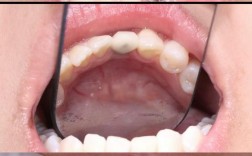

即刻种牙的核心优势在于“拔牙即种植”,将传统种植的两步(拔牙后等待3-6个月骨愈合,再植入种植体)合并为一步,手术时间显著缩短,手术当天,患者需进行局部麻醉(注射麻醉约5-10分钟),确保术中无痛,随后,医生会小心拔除患牙,尽量保护牙槽骨壁的完整性(若骨壁破损严重,可能无法即刻种植),彻底清创拔牙窝,避免残留炎症组织。

使用专用种植备洞工具在牙槽骨内制备种植窝,根据骨质硬度调整转速和冷却,避免骨损伤(此步骤约10-30分钟),随后将种植体旋入种植窝,植入扭矩需达到理想值(通常35-45N·cm,确保初期稳定性),若骨条件允许,可能同期安装愈合基台或临时基台(为后续戴临时牙冠做准备),手术全程严格遵循无菌原则,创伤较小,通常单颗牙的即刻种植手术时间控制在1-2小时内,多颗牙种植可能需2-3小时,术后患者需留院观察30分钟,无异常即可离院。